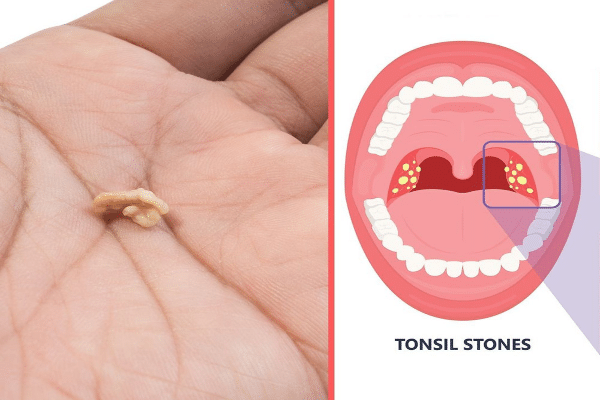

Οι πέτρες των αμυγδαλών ή οι αμυγδαλόλιθοι είναι μικροί, ασβεστοποιημένοι σχηματισμοί που αναπτύσσονται στις σχισμές των αμυγδαλών. Αυτές οι πέτρες αποτελούνται από υπολείμματα όπως νεκρά κύτταρα, βλέννα, σωματίδια τροφής και βακτήρια, τα οποία συσσωρεύονται και σκληραίνουν με την πάροδο του χρόνου. Οι πέτρες αμυγδαλών μπορεί να ποικίλλουν σε μέγεθος, από μικροσκοπικούς κόκκους έως μεγαλύτερους, πιο εμφανείς σχηματισμούς και συχνά έχουν λευκό ή κιτρινωπό χρώμα.